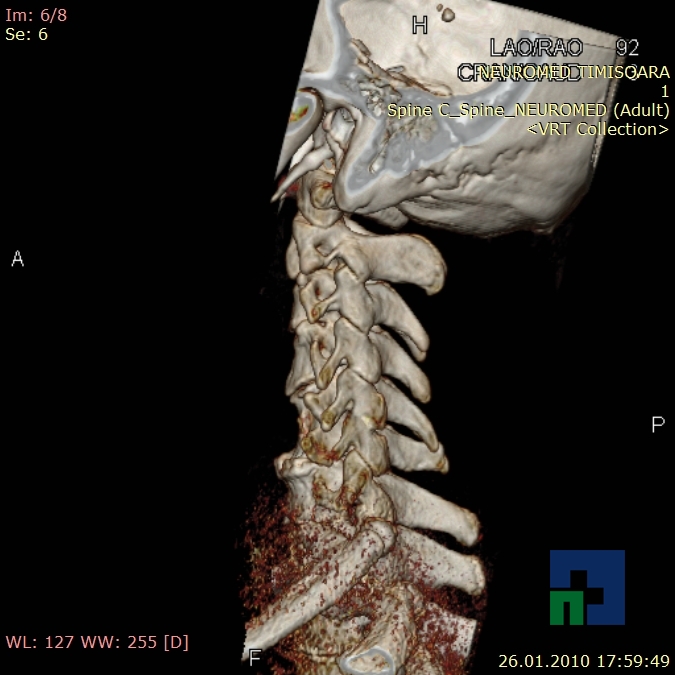

- Diagnosticul fracturilor:

- Unice

- Multiple

- Cu înfundare

- Complexe cranio-sinusale

- Complexe cranio-etmoidale

- Complexe cranio-orbitare

- Complexe cranio-faciale